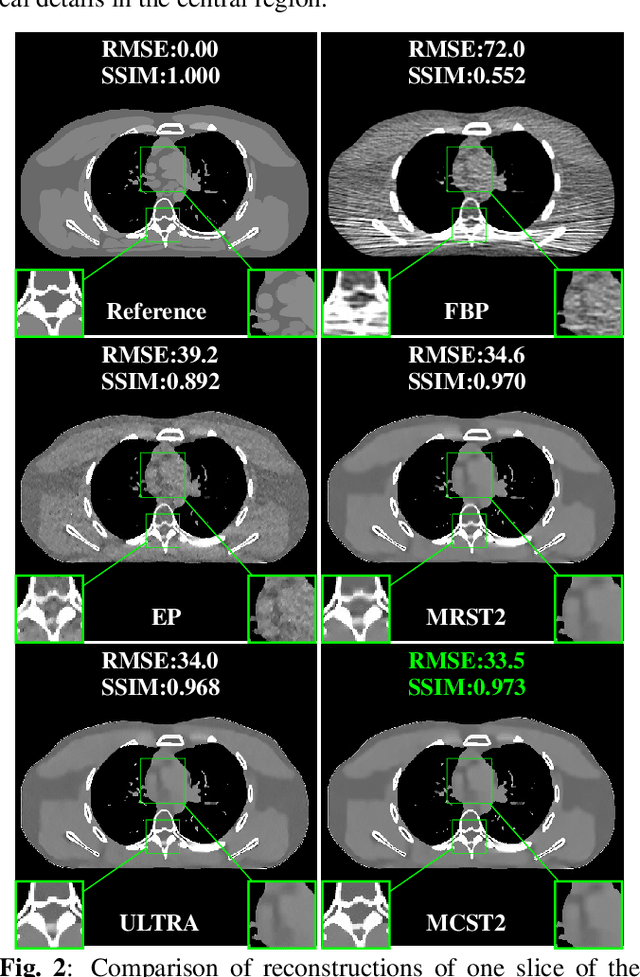

Achieving high-quality reconstructions from low-dose computed tomography (LDCT) measurements is of much importance in clinical settings. Model-based image reconstruction methods have been proven to be effective in removing artifacts in LDCT. In this work, we propose an approach to learn a rich two-layer clustering-based sparsifying transform model (MCST2), where image patches and their subsequent feature maps (filter residuals) are clustered into groups with different learned sparsifying filters per group. We investigate a penalized weighted least squares (PWLS) approach for LDCT reconstruction incorporating learned MCST2 priors. Experimental results show the superior performance of the proposed PWLS-MCST2 approach compared to other related recent schemes.